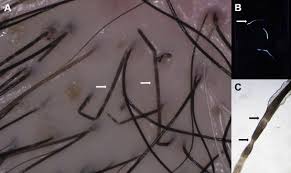

Hair follicles also anchor hair to your skin. This is when the whole follicle gets infected after shaving. An old razor does not cut the hairs away from the skin but yanks them out, causing minimal blood loss that causes the black dots in hair follicles after shaving. Not unexpectedly the new hair follicles were accompanied with skin tumors. A look at the clogged hair follicle, causes, cyst, hardened sebum, blocked, how to open, on legs, arms, groin and buttocks. It resides in the dermal layer of the skin and is made up of 20 different cell types, each with distinct functions. This is a video taken with a scope of exclamation mark hair extruding, which is seen in the bald area of alopecia areata. 3a, the observed primary and secondary follicles are shown as the red dots and black circles, respectively.

Spatial regularity in hair follicle patterns as revealed by voronoi analysis. Unfortunately, i learned that rule well. A look at the clogged hair follicle, causes, cyst, hardened sebum, blocked, how to open, on legs, arms, groin and buttocks. That's the shaved off part of the hair and since you obviously have dark hair, it's going to show especially as the hair grows back. Black dots are seen in other conditions besides alo. They are commonly observed in alopecia areata 3, dissecting cellulitis 4, 5. Black dots on the skin can show up as a sign of liver damage. In the mouse this is true for most body areas such as back skin. An old razor does not cut the hairs away from the skin but yanks them out, causing minimal blood loss that causes the black dots in hair follicles after shaving. The hair follicle regulates hair growth via a complex interaction between hormones, neuropeptides, and immune cells. The pimples may have pus in them, and they may itch or burn. I went to the derm and she thinks it you'll never get rid of it. Black dots represent hair follicles broken off at the level of the skin surface.

This causes hair follicles to swell into inflamed hair follicles usually looks like red pimples with a hair in the center of each one. Dots correspond to hair follicle openings observed in trichoscopic examination 1. Whatever the reason, there are treatment methods to. The hair follicle regulates hair growth via a complex interaction between hormones, neuropeptides, and immune cells. Moisten leg hair for two to three minutes before shaving. In milder cases, a dog's skin may have small, inflamed areas filled with pus. This moisturizing helps hair follicles grow through skin properly. Black dots on the skin can show up as a sign of liver damage.

The next topic of interest will be. You have hair follicles just about everywhere except your lips, your palms, and the soles of your feet. Understanding how hair follicle drug tests work and how long marijuana can be detected will help you make the best choices should you need to pass a hair follicle drug test. Vertical dotted lines delimitate hair follicle length at time 0. The liver is a major organ in the body and its main function is to remove the toxic substance from the blood. What causes a clogged hair follicle? Black dots on the skin can show up as a sign of liver damage. Whatever the reason, there are treatment methods to. Check out our black dots hair clip selection for the very best in unique or custom, handmade pieces from our shops. During the career of any seasoned weed smoker, there comes a dreaded time when you'll have to pass a drug test. Black dots are seen in other conditions besides alo. Black dots correlate with disease activity in alopecia areata and are a negative prognostic factor. What causes infected hair follicle?